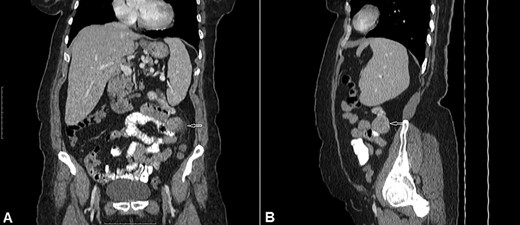

Histology showed a mixed cell type jejunal GIST with a mitotic index of <5/50 HPF—High Power Fields, clear resection margins and an intact tumour capsule (Figs 4 and 5).

Gross pathology: well-circumscribed extraluminal mass (4 × 3.5 × 3) cm; cut surface is smooth, tan and firm with lobulated appearance, hemorrhagic and necrotic areas.

Hematoxylin and eosin stain (A) Jejunal mass at ×4 magnification, (B) jejunal mass at ×40 magnification: consist of spindle cells of varying cellularity, hyperchromatic and nuclear pleomorphism with areas of epithelioid cells (mixed type GIST).